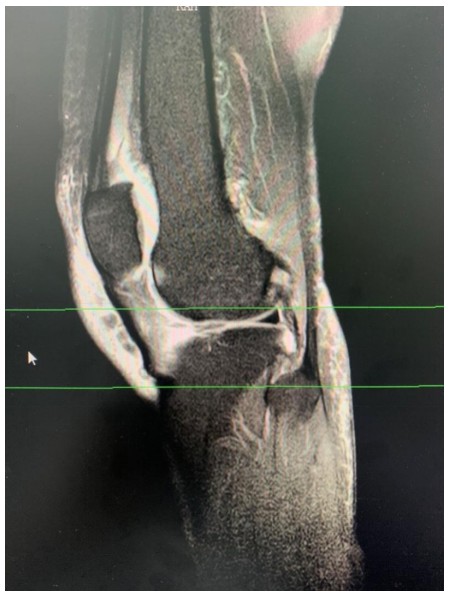

近日,衡陽市中心醫(yī)院華新院區(qū)疼痛門診接診了兩位年齡相仿、癥狀相似的女性患者,兩人都因一側(cè)膝關(guān)節(jié)腫脹、變形,疼痛難忍、下蹲受限、步行困難嚴(yán)重影響生活前來求診。兩位患者分別經(jīng)過張娟、趙夢岑兩位主治醫(yī)生的診治后被診斷為膝關(guān)節(jié)退變,并且發(fā)現(xiàn)患膝側(cè)關(guān)節(jié)內(nèi)存在大量積液。

膝關(guān)節(jié)炎是一種以退行性病理改變?yōu)榛A(chǔ)的疾患,好發(fā)于中老年人群,其癥狀多表現(xiàn)為膝關(guān)節(jié)腫痛、坐起立行時(shí)膝部酸痛不適等,偶有腫脹、彈響、積液等表現(xiàn)。如不及時(shí)治療則會(huì)導(dǎo)致關(guān)節(jié)畸形或殘疾。專家提醒,患有膝關(guān)節(jié)炎請(qǐng)及時(shí)到正規(guī)醫(yī)院就醫(yī),切莫因拖延耽誤了治療時(shí)機(jī)。